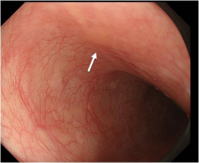

通常光による食道の観察像例